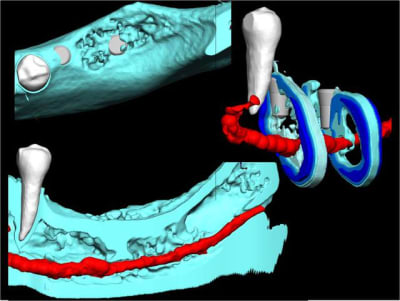

Il commence au trou mentonnier qui est situé à l'apex de la 6 ( rare) de la 5 ou de la 4, et il assure l'innervation du bloc IC. Il est conseillé de le respecter sur ses 4-6 premiers mm pour éviter une lésions nerveuse pouvant mal cicatriser et provoquer des décharges de neuro transmetteurs, d'où des douleurs cédant très difficilement aux antalgiques

Pour visualiser le trou mentonnier, il convient de décoller le périoste pour le mettre en évidence si tu as peur d'être trop proche. Le voir c'est l'éviter !

tu montres l'innervation de la PM et ... ?

Tu peux le voir comme cela ou tient si j’ai un cas similaire quel sont les solutions. ..distraction, greffe de pariétal, greffe allogène, PPA, rien…. Un praticien ma demandé de faire un guide pour une réhabilitons complète mandibulaire avec 2 implants position 36, 46 de 10mm. Ma réponse mais Docteur cela ne passe pas « si, ils seront bi-cortical » (l’apex de l’implant devait éffracter légèrement la zone ou passe l’artère linguale). Je ne pense pas que cette démarche soit courante, qu’elle se renouvellera fréquemment mais maintenant je sais qu’elle est réalisable.